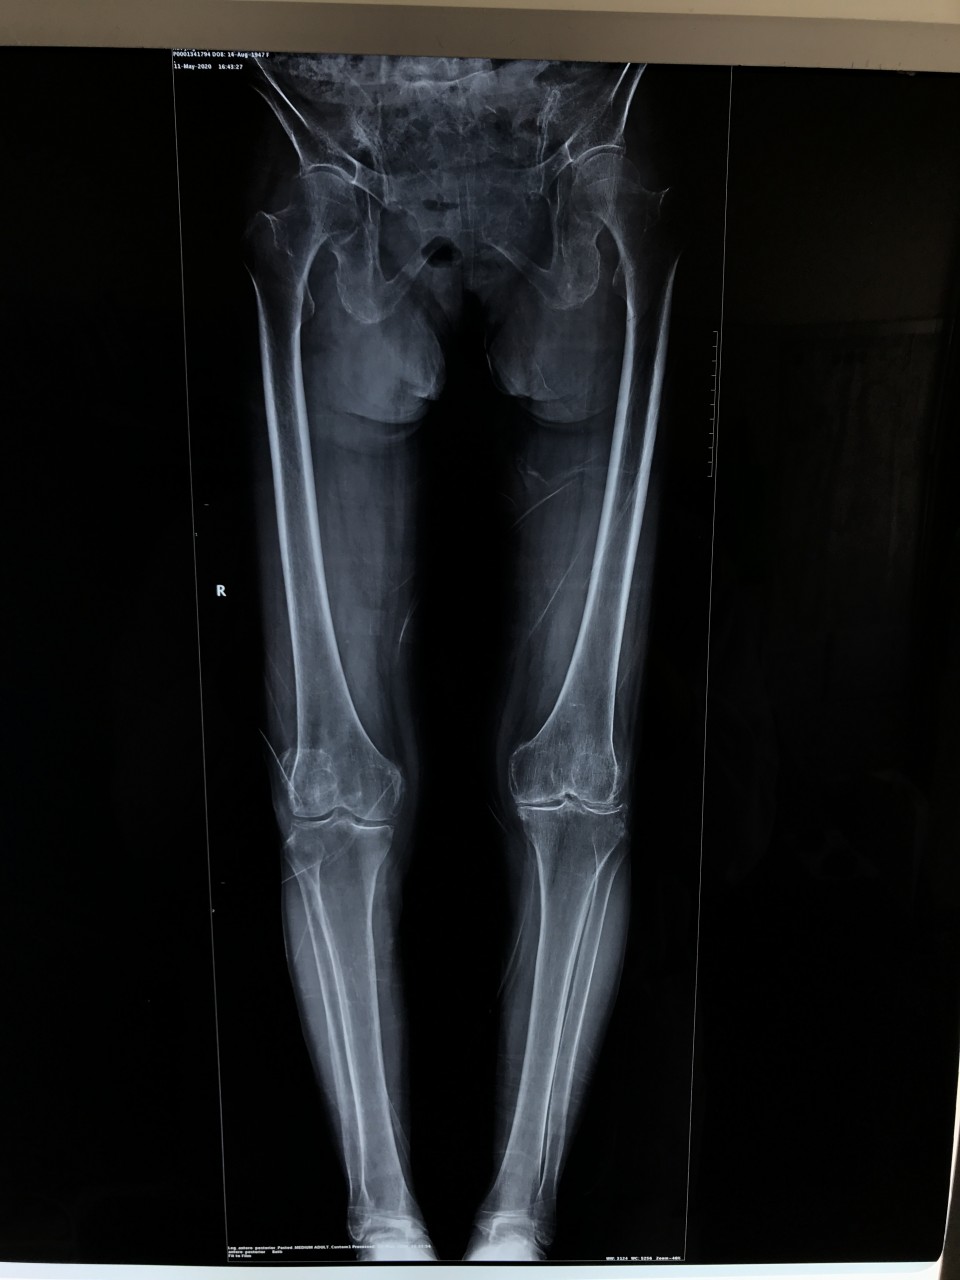

5月11日,一位72岁女性患者因“双膝关节疼痛伴活动受限8年,加重半年”入院,术前摄片提示双侧膝关节骨性关节炎。左侧膝关节伸直型僵直,屈伸活动度范围为0°。 我科胡孔足主任术前结合患者病史,体检及辅助检查,制定详实方案,先行左侧全膝关节置换术,术中采用TTO(胫骨结节截骨术),患者术后第二天下地正常行走,5月18日出院时已经能够完全自主抬腿,膝关节屈曲可达100°,减轻了患者的疼痛,明显提高了生活质量,疗效满意。